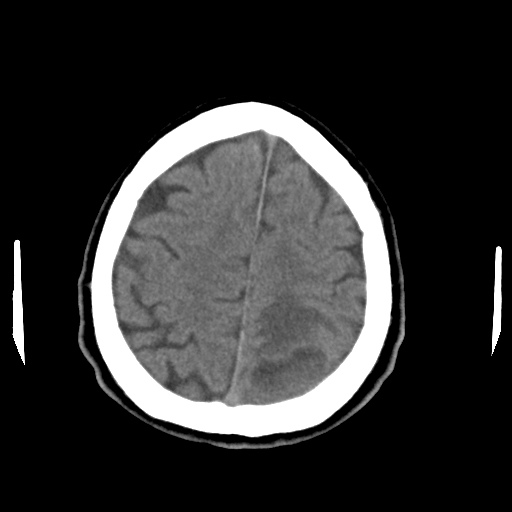

Caso neurorradiología

Paciente de 60 años con cuadro de 1 semana de evolución consistente en tropiezos frecuentes y alteración en la movilidad del miembro

inferior derecho. No refiere

cefalea u otros síntomas asociados, no pérdida de peso, no náuseas o emesis, no

sudoración nocturna. Antecedentes de hipertensión arterial y diabetes.

Resonancia magnética

Escanografía